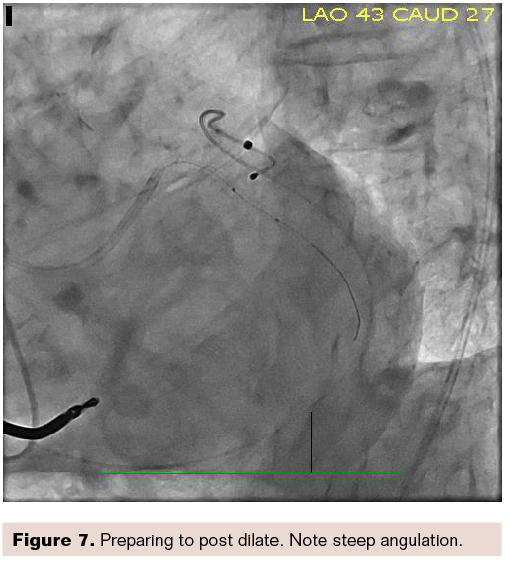

Figure 7, again, shows steep angulation, but the stent is clearly visible. We are preparing to post dilate. Figure 8 shows the final result.